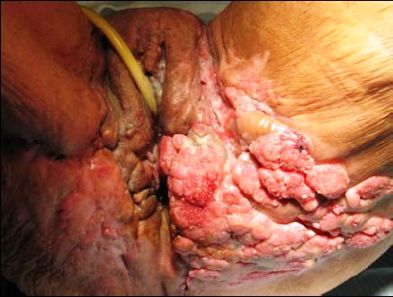

Pacientka D.V., 56 let, byla poprvé hospitalizována 29.6.2006 na interním oddělení pro otok LDK. V anamnéze neudávala žádnou pozoruhodnost. Rodina pozorovala asi rok změnu psychického stavu a sklon k abusu alkoholu. Gynekologicky naposledy vyšetřena asi před 10 lety. Při vyšetření shledány verukózní výrůstky v okolí zevního genitálu a anu a zvětšení tříselních lymfatických uzlin(Obr.1).

Obrázek 1